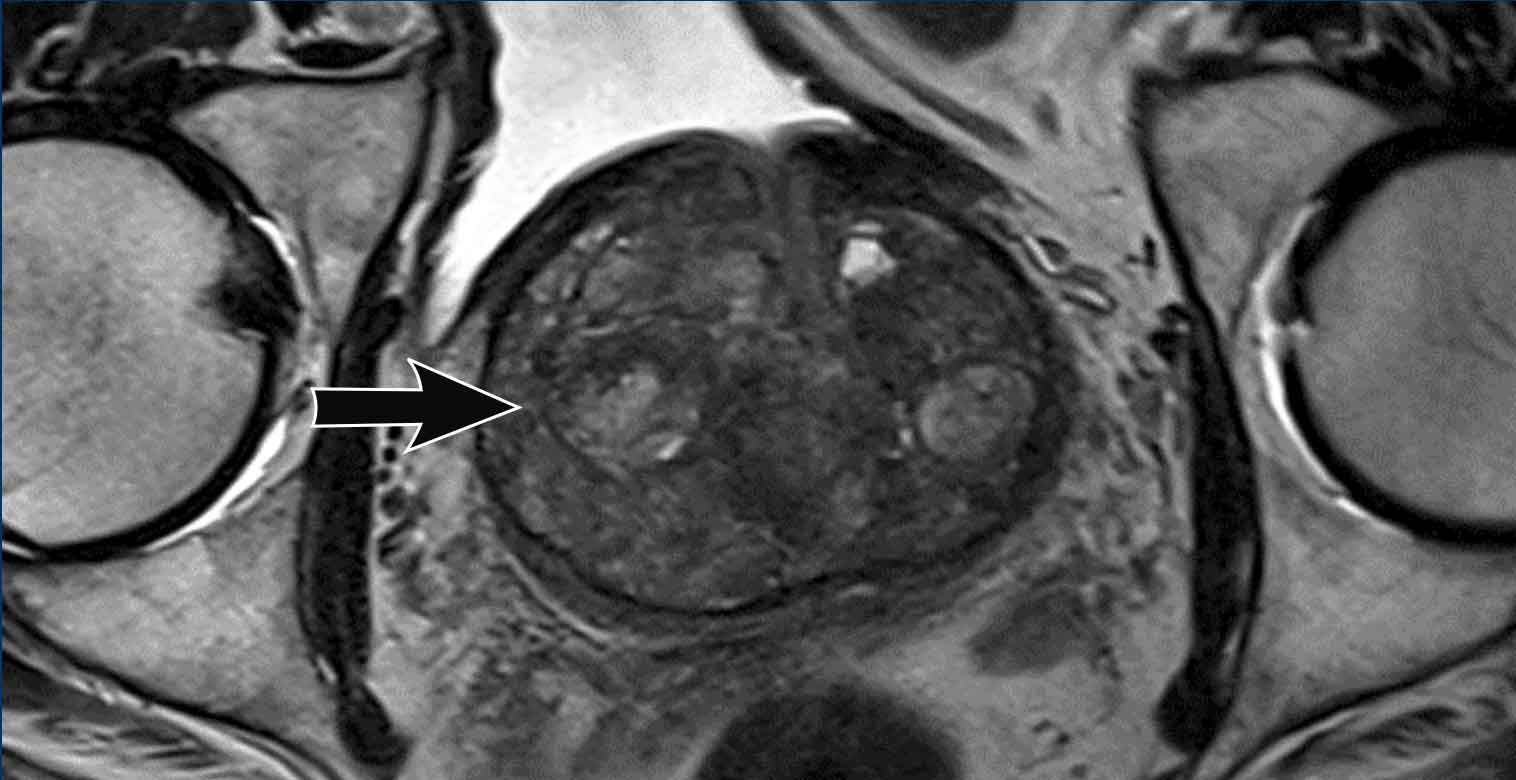

Pi rads v 2.1